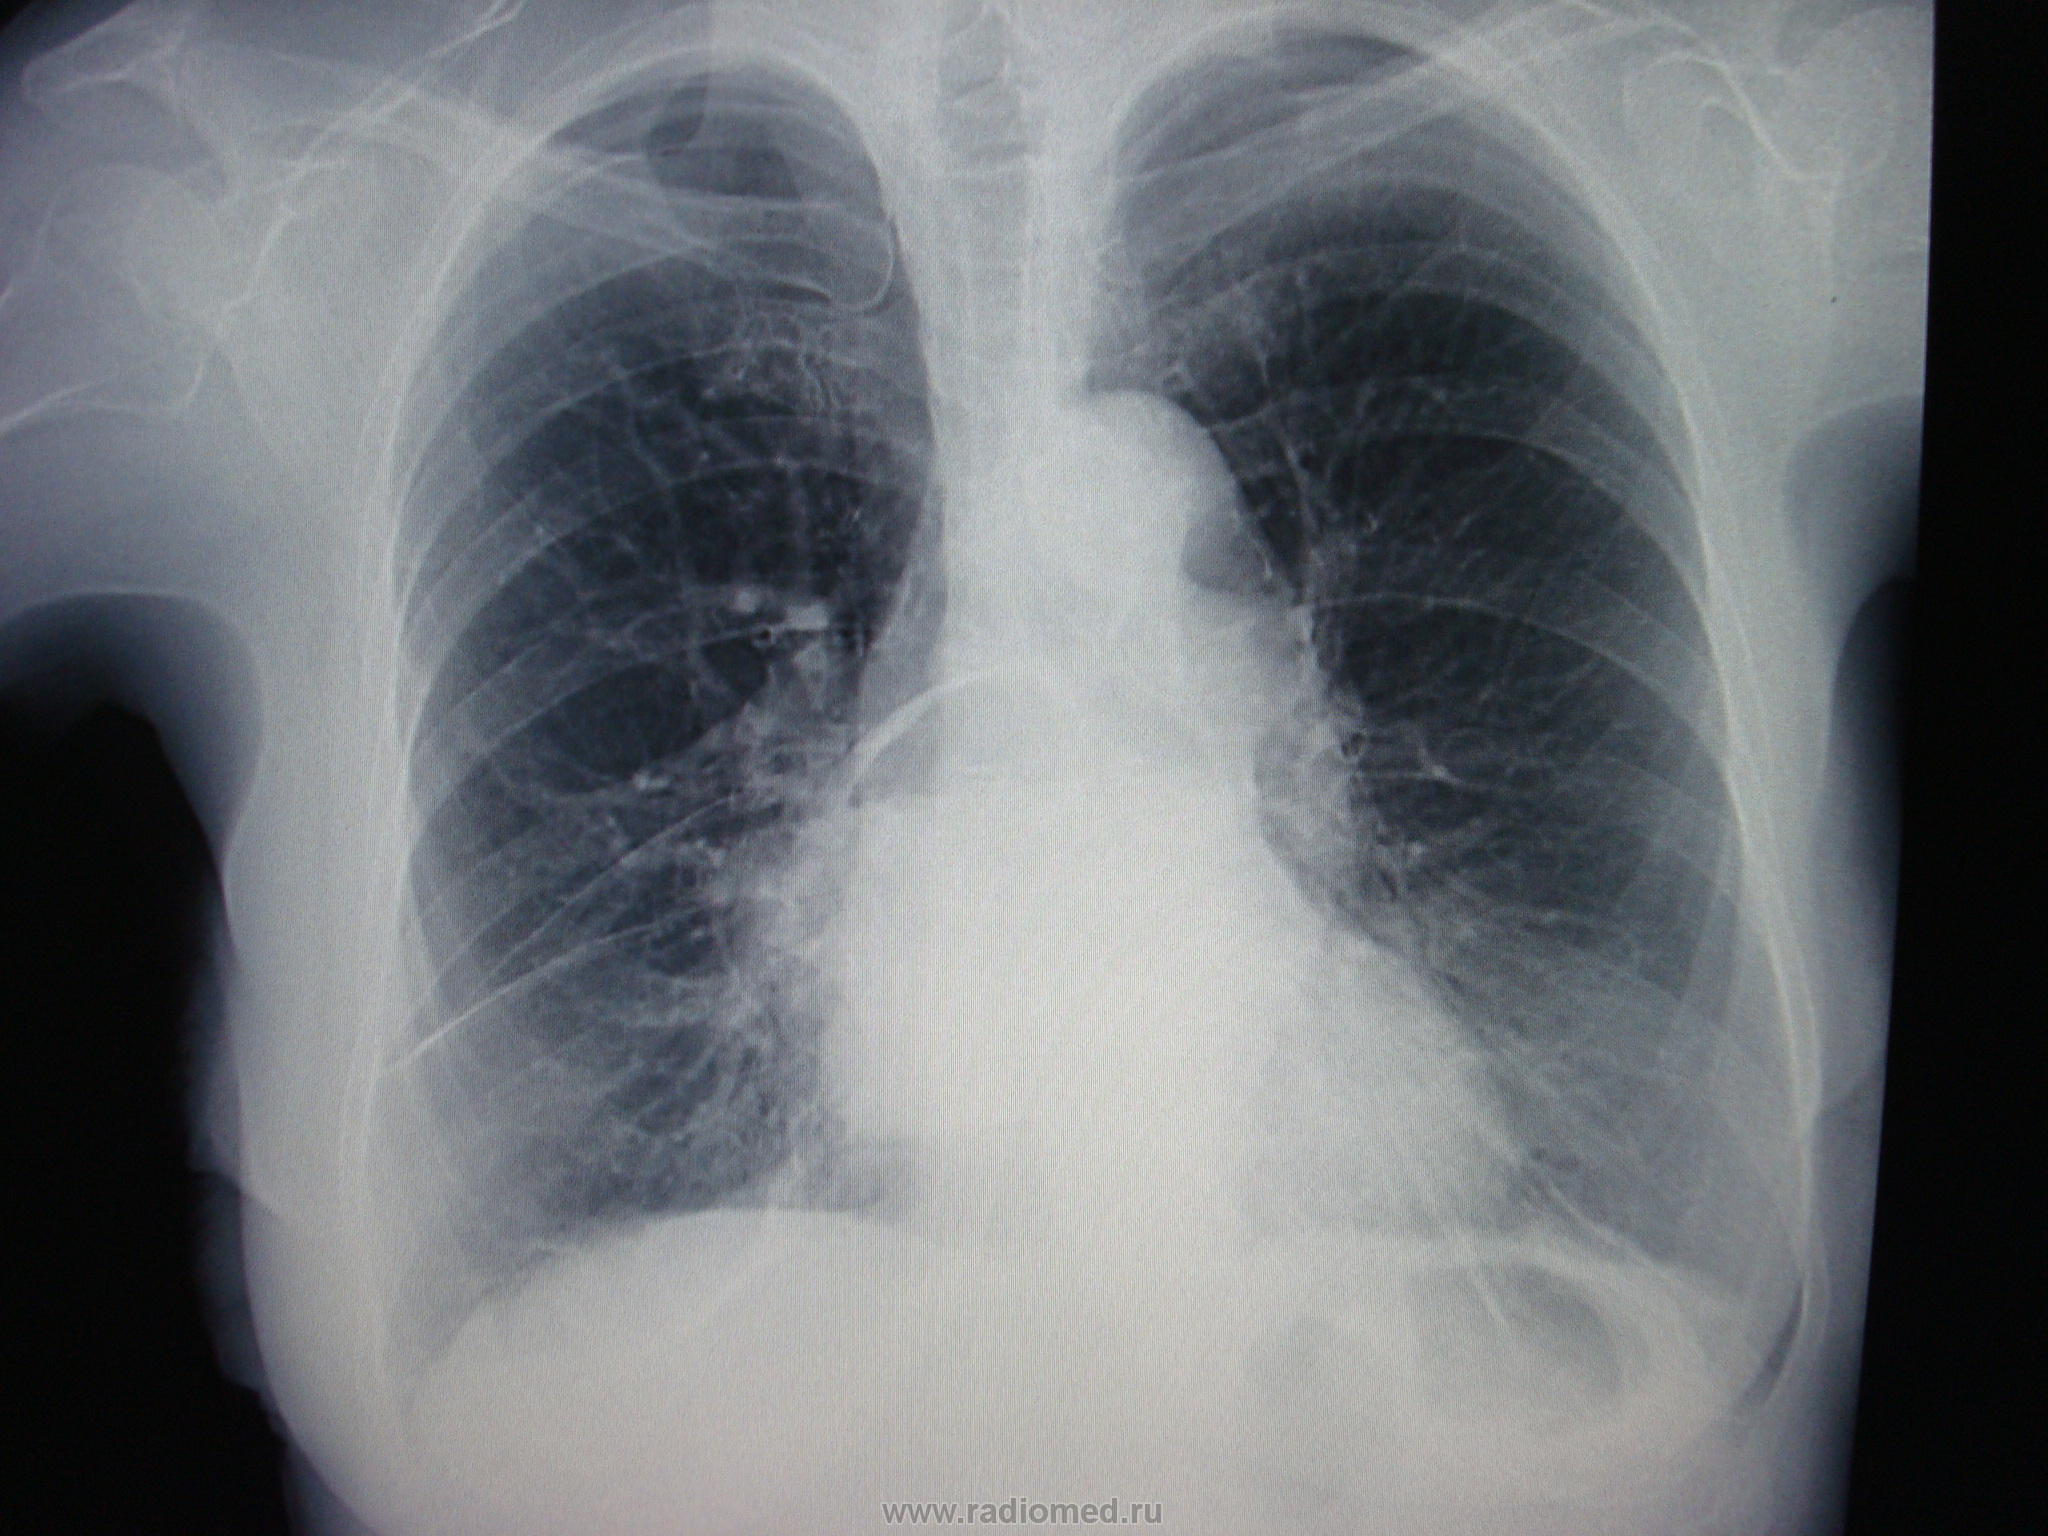

Материалы , которые представлены даны и записаны со слов врача терапевта. Когда  увидел, то вспомнил "Киллиан-Джеймисон-дивертикул" на нашем сайте. История заболевания. 2001 год. 60 лет. После сильного переохлаждения (провал под лед) - озноб, температура 38С, боль в грудной клетке справа, сухой кашель. Лечение народными средствами без эффекта.При кашле стало выделятся много гнойной мокроты с прожилками крови, температура повысилась до 40 С.  При поступлении в стационар тяжелое состояние. Диагноз - абсцесс легкого. Результат лечения (через 1 мес.) представлен на рис.2. Другой рентгенологической документации, к большому сожалению, нет. С уважением Nicolas

risunok_2.jpg

Хорошая динамика.